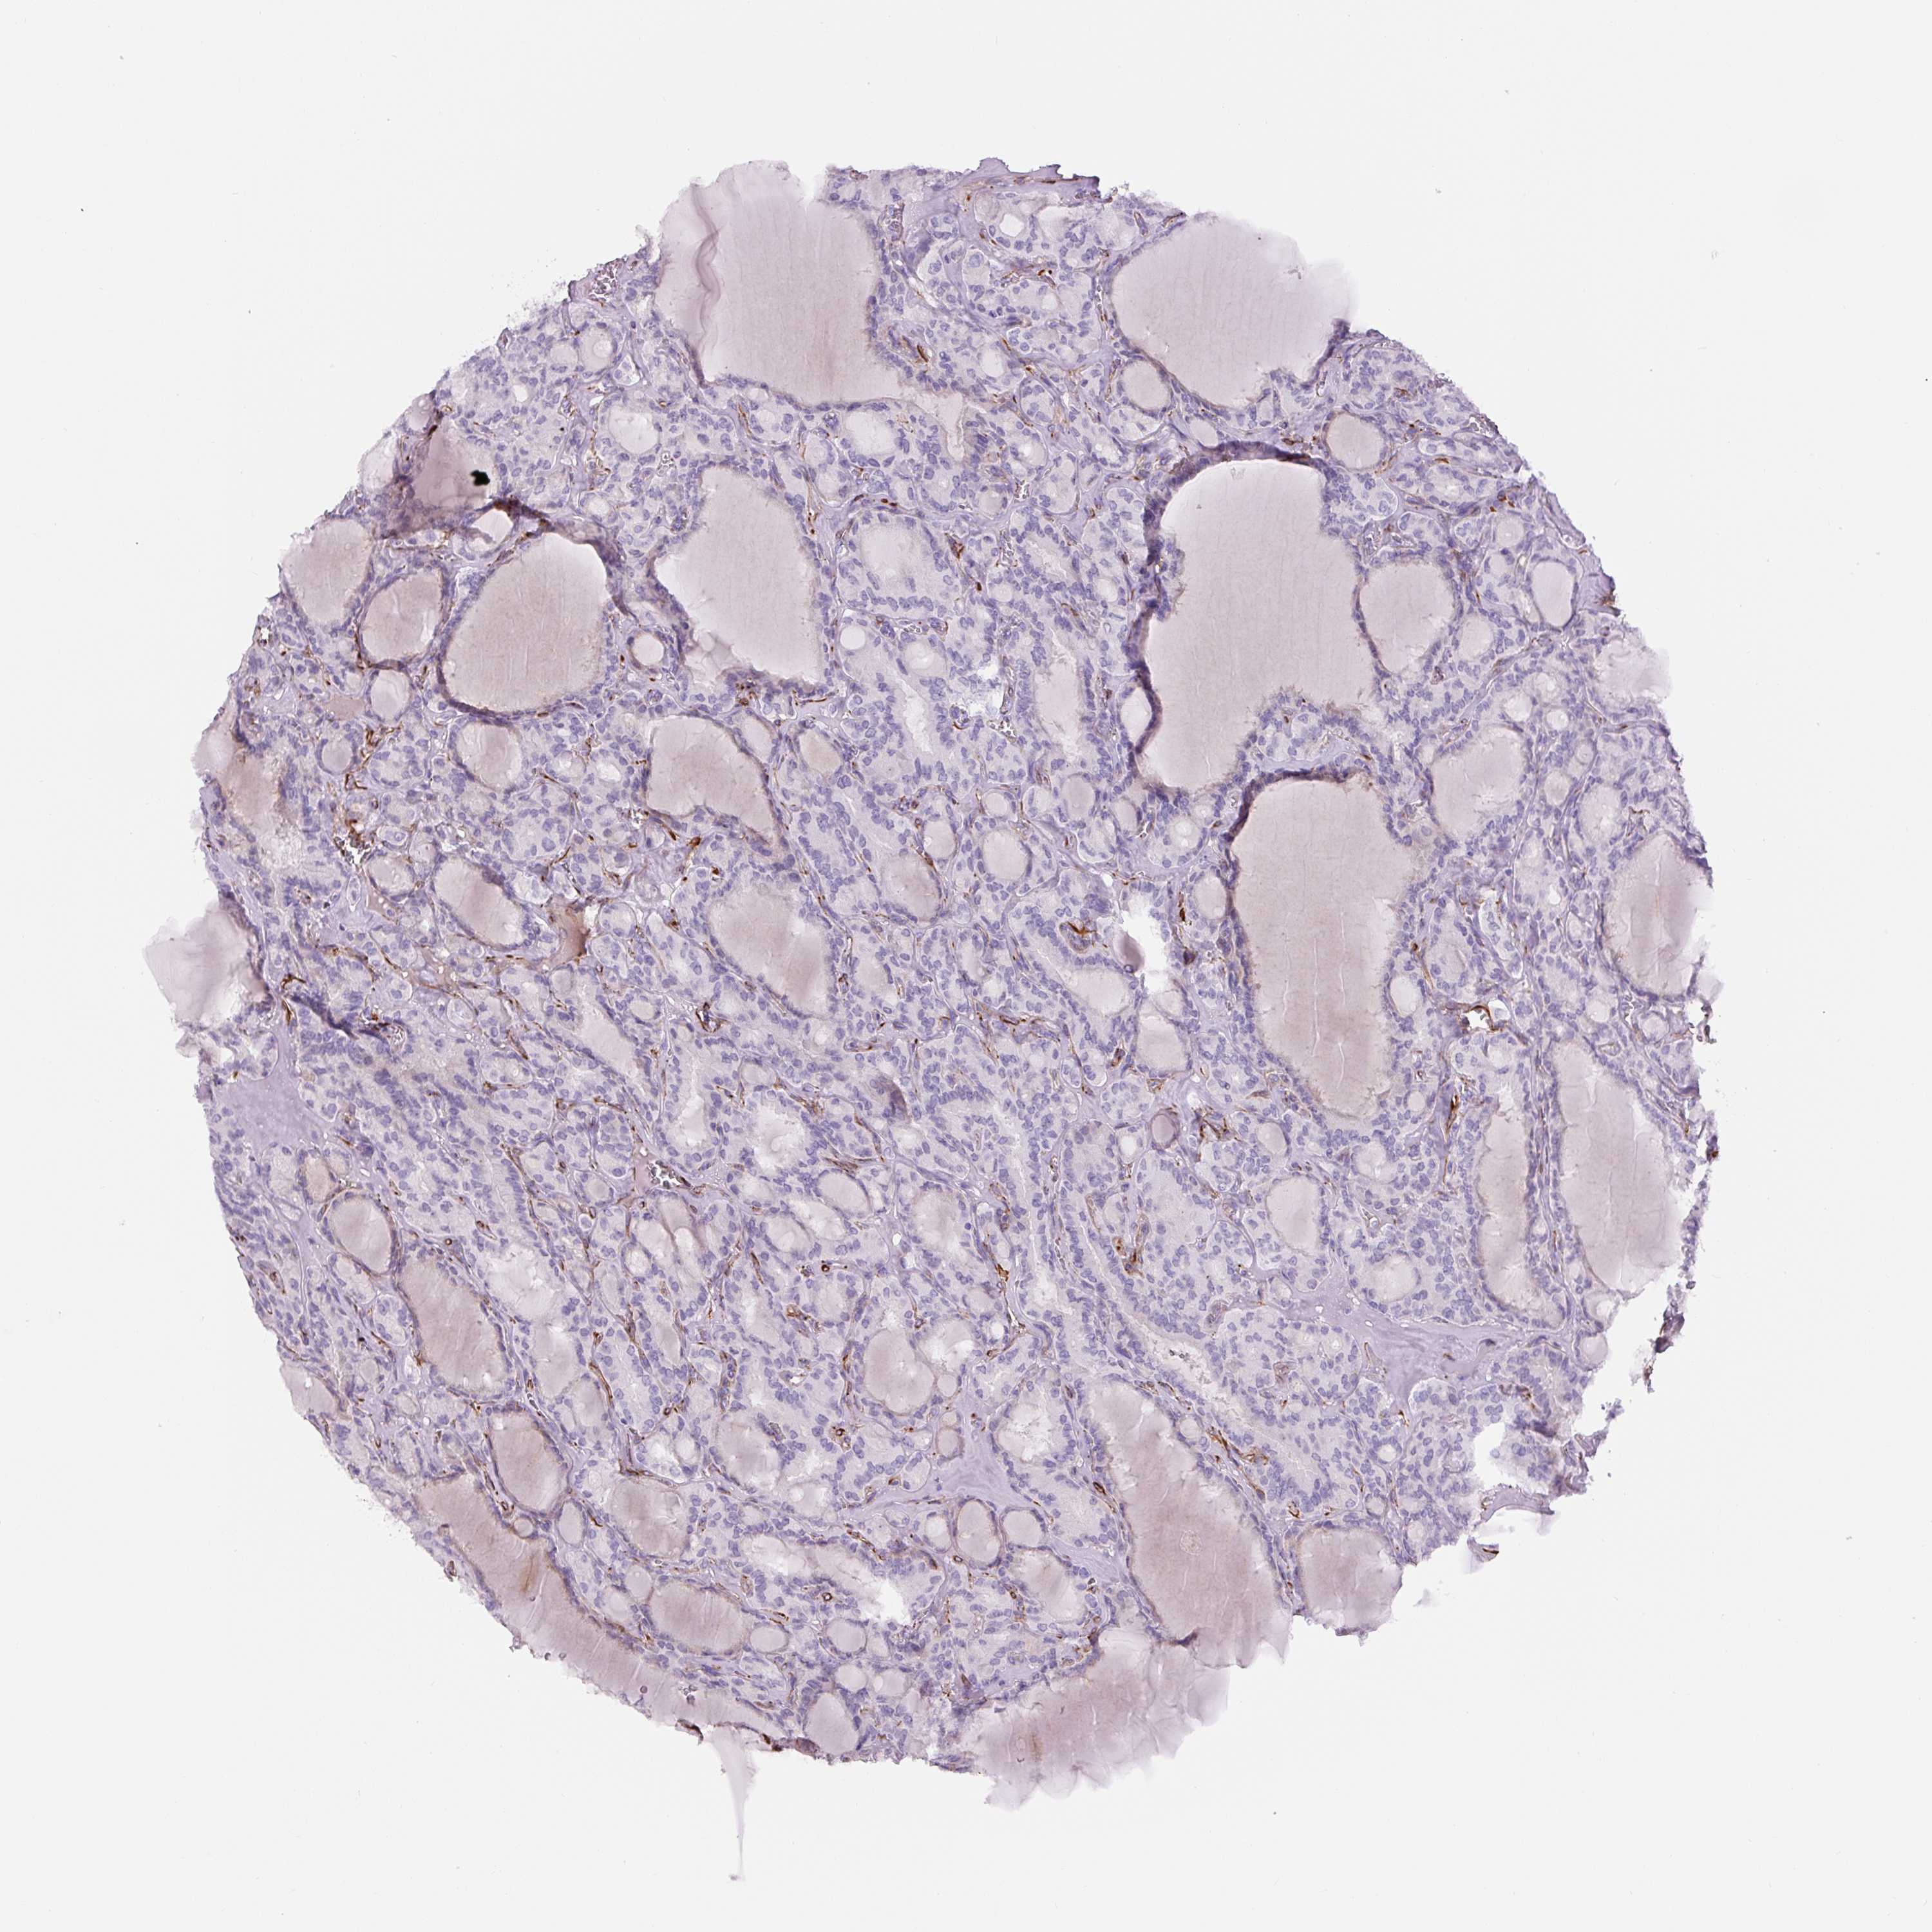

THYROID CANCER - Protein expressioni

A mouse-over function shows sample information and annotation data. Click on an image to view it in a full screen mode. Samples can be filtered based on level of antibody staining by selecting one or several of the following categories: high, medium, low and not detected. The assay and annotation is described here.

Note that samples used for immunohistochemistry by the Human Protein Atlas do not correspond to samples in the TCGA dataset.

Antibody stainingi

Antibody staining in the annotated cell types in the current human tissue is reported as not detected, low, medium, or high, based on conventional immunohistochemistry profiling in selected tissues. This score is based on the combination of the staining intensity and fraction of stained cells.

Each image is clickable and will lead to virtual microscopy that enables deeper exploration of all samples and also displays staining intensity scores, fraction scores and subcellular localization as well as patient and tissue information for each sample.

Antibody HPA007007

Antibody HPA026111

Antibody CAB005889

Antibody CAB058692

Staining

High

Medium

Low

Not detected

Intensity

Strong

Moderate

Weak

Negative

Quantity

>75%

75%-25%

<25%

None

Location

Nuclear

Cytoplasmic/membranous

Cytoplasmic/membranous,nuclear

Papillary adenocarcinoma, NOS

Follicular adenoma carcinoma, NOS